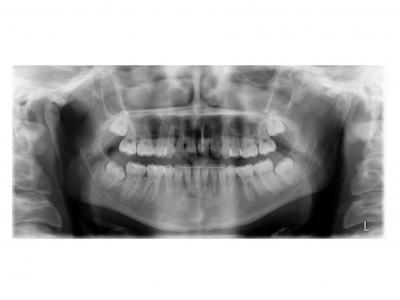

Voici les deux patientes traitées

Ici, dans les deux cas, les deuxièmes prémolaires ont été extraites et les traitements ont duré 18 mois.

Dans le deuxième cas, le désencombrement a fermé les espaces en 6 mois. Les incisives ont été surtorquée pour avoir un meilleur soutien labial. Le traitement qui avait bien débuté, a été difficile à finir, car les anatomies coronaires et radiculaires étaient perturbées.

Si on n'avait pas extrait dans le premier cas, cela imposait une ouverture de l'espace de la 24 et donc une avancée des incisives supérieures et donc une aggravation de la béance. Dans le deuxième, on sortait les racines de l'os alvéolaires (racines déjà apparentes au départ). Même une expansion associée à du stripping et une distalisation des secteurs latéraux n’auraient pas permis de préserver ce parodonte fin.